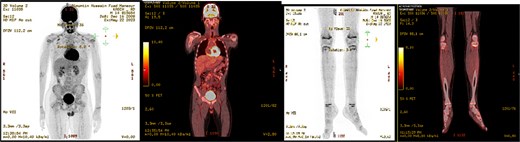

Post-operative course, patient improved during the admission with smooth post-operative course, discharged in good condition and was started to follow with the hematology clinic after the final histopathological results. A subsequent Pan CT, positron emisssion tomography (PET) scan showed no evidence of metastasis or residual disease (Fig. 6).

PET scan showed no evidence of hypermetabolic malignancy or lymphoproliferative disease or residual disease.